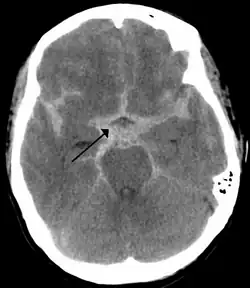

![]() Obraz tomografii komputerowej głowy pacjenta z krwotokiem podpajęczynówkowym (widoczny jako biała plama na środku mózgu) | |

Krwotok podpajęczynówkowy (ang. subarachnoid hemorrhage, łac. haemorrhagia subarachnoidalis) – krwawienie do przestrzeni podpajęczynówkowej, która znajduje się między pajęczynówką a oponą miękką mózgu. Krwawienie występuje niespodziewanie, zwykle z powodu pękniętego tętniaka mózgu lub jako skutek urazu głowy.

Oprócz dokładnego badania lekarskiego wykonuje się tomografię komputerową głowy, badanie krwi oraz płynu mózgowo-rdzeniowego, który często jest jednolicie podbarwiony krwią oraz ksantochromiczny[8].